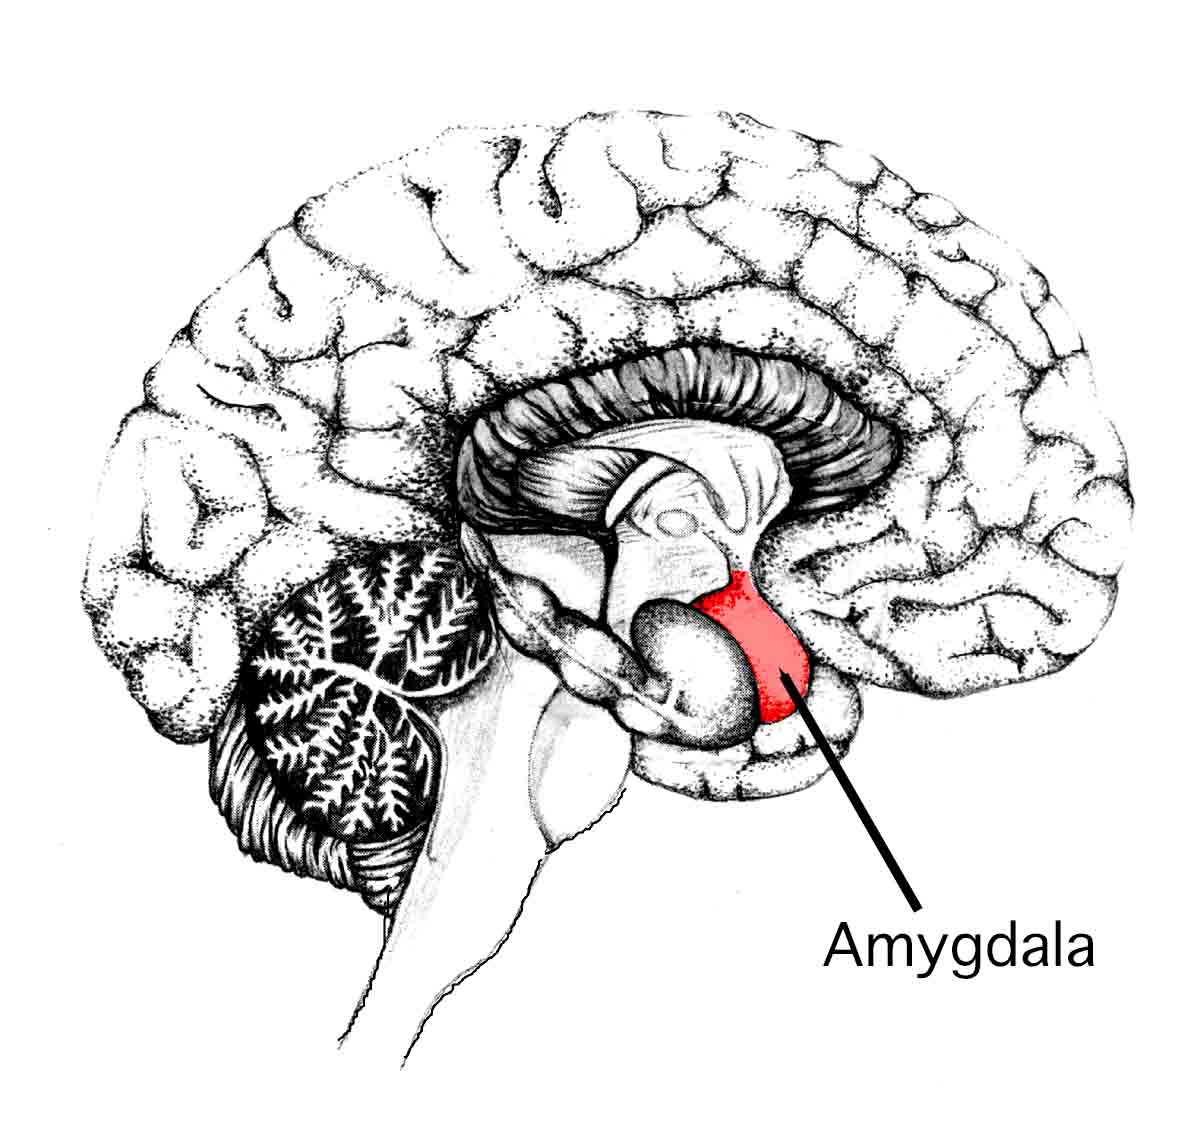

The amygdala consists of a pair of structures, each of which has the shape of an almond; these two structures are found in the middle side of the temporal lobe of the brain. Each pair making up the amygdala consists of three nuclei. The nuclei are a group of specific nerve cells (neurons) that work together; in the amygdala these three are: centromedial, cortical-like, and basolateral groups. The amygdala is part of the limbic system of the brain, which consists of several structures dealing with various aspects of memory and emotion.

The hippocampus can be divided into three regions, the ventral, dorsal, and intermediate. The hippocampus is also found in the middle region of the temporal lobe but it has a seahorse shape that is different from that of the amygdala. Like the amygdala, it is part of the limbic system but it has a different shape and function. The similar location to the amygdala can lead to confusion of the hippocampus with the amygdala.

The amygdala occurs as two areas found in the middle part of the temporal lobes of the brain in front of the hippocampus. The hippocampus occurs as two areas found in the middle part of the temporal lobes behind the amygdala.

The amygdala is the shape of an almond. The hippocampus is the shape of a seahorse.